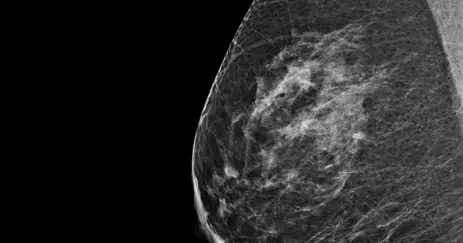

Bi-Rads B

The breast tissue is mostly fatty tissue with some scattered areas of fibroglandular density. The breast tissue is not dense.